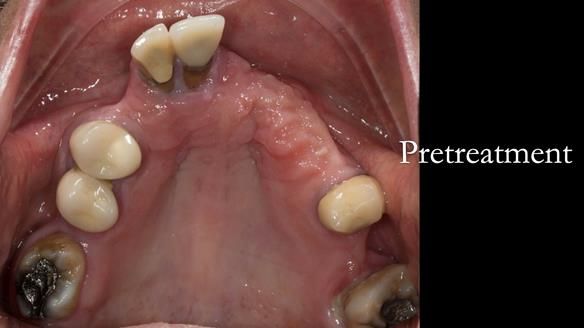

Aesthetically and functionally poor RPDs were replaced for Eileen, a 74 year old woman.

Referred to me by her general dental practitioner specifically for replacement RPDs.

Diagnoses

- Missing teeth in the upper and lower jaws

- Upper and lower metal based RPDs, poorly fitting, worn occlusal surface, reverse curve aesthetics, lacking support

- Poor dental appearance with reverse incisal curve

- The upper right central and lateral incisors with post crowns. Healthy and functionally secure but with poor appearance, contributing to the reverse curve.

- Moderate to heavily restored dentition with deep overbite (Class 2 div II)

- Decoronate post crowns upper right lateral and central incisors to use as over denture abutment supports

- Add upper right lateral and central incisor denture teeth to existing upper RPD as temporary measure during making of new RPDs